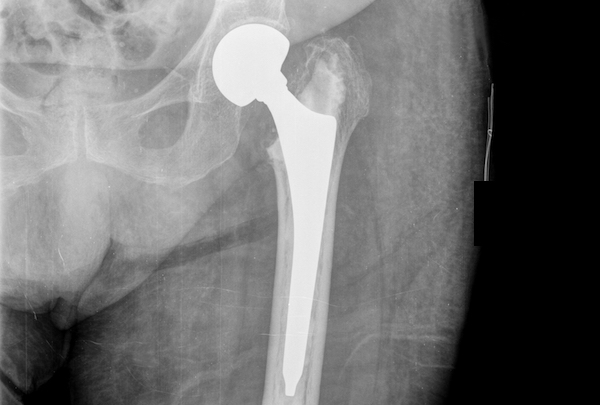

A closed reduction should be attempted, in the interest of time. 23 hip dislocations require urgent reduction because the vascular supply to the femoral head may be compromised. Your upper femur and the socket in your pelvic bone are replaced with artificial parts (prostheses).

Surgical dislocation approach has shown some promise in improving the. Currently, the method most surgeons use for treating femoral shaft fractures is intramedullary nailing. Revised distal humerus module is.

During this procedure, a specially designed metal rod is inserted into the canal of the femur. Stop any moderate activity and repetitive, stressful exercises (running, squatting, cycling). Courses, webinars, and online events, in your region or worldwide.